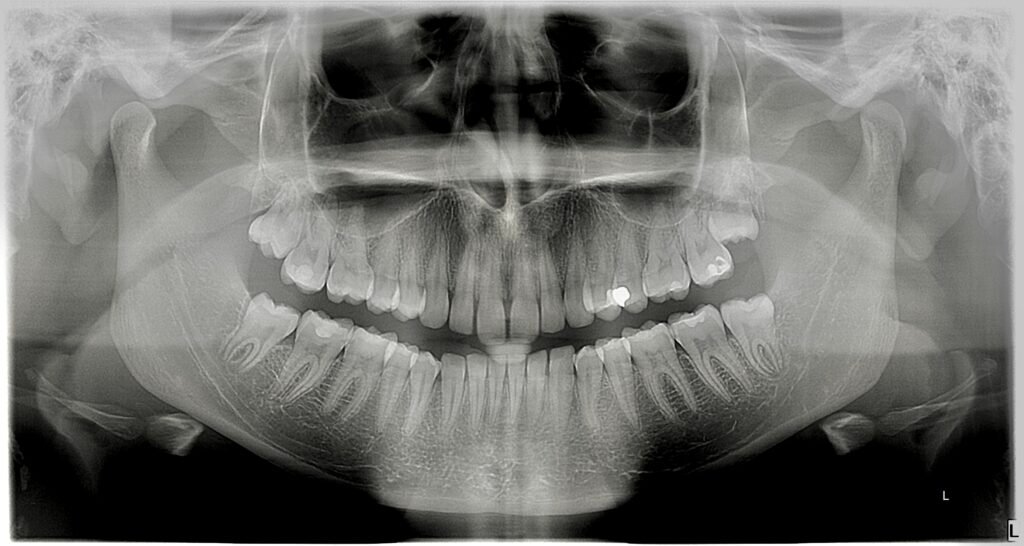

• Ortopantomogram (panoramska snimka): Cjelovit prikaz čeljusti i zuba, potreban za prvi pregled, vađenje zuba kod oralnog kirurga, za ortodonciju i čitav niz ostalih stanja i bolesti zubi i usne šupljine te se smatra najčešćom snimkom digitalne zubne dijagnostike. Ortopan snimka u svakodnevnoj praksi među doktorima dentalne medicine je sinonim za ZUBNI RENDGEN

Koliko je zračenja u jednom ortopanu?

• Efektivna doza zračenja: Tipično se kreće između 5,5 i 22 mikro-Sieverta (µSv), što odgovara otprilike 1–5 dana prirodnog pozadinskog zračenja(dakle najnormalnijeg boravka na otvorenom).

• U poređenju sa drugim rendgenskim snimcima:

• Bitewing (mali rendgenski snimak): oko 0,005 mSv (1 dan pozadinskog zračenja).

• CT skener: oko 2 mSv (1 godina pozadinskog zračenja).

Praktične informacije

• Trajanje procedure: Snimanje traje oko 12–20 sekundi, tokom kojih se X-ray aparat rotira oko glave pacijenta.

• Zaštita pacijenta: Obično se koristi olovni prsluk kako bi se dodatno smanjila izloženost zračenju.

• Sigurnost: Zračenje u ortopanu je mnogo niže nego kod CT skenera ili medicinskih rendgenskih snimaka, poput rendgena grudnog koša, koji ima dozu od 0,02 mSv.

Zaključak

Ortopan pruža detaljan pregled dentalnih i maksilofacijalnih struktura uz minimalnu izloženost zračenju. Efektivna doza je niska i ne predstavlja značajan rizik za zdravlje.

Primjer jednog ortopana